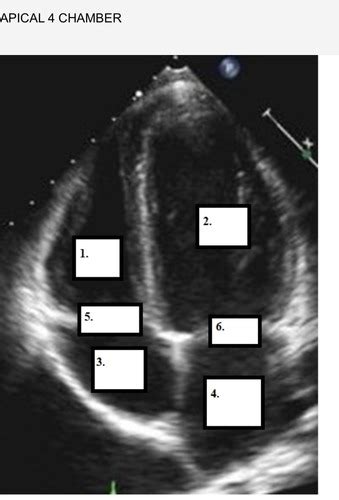

So, why is the apical view echo probe position so darn important? Well, imagine trying to understand how a car engine works by only looking at it from the side. You’d miss a ton of crucial details about how the pistons move, how the valves open and close, and the overall efficiency of the system. The apical view is kind of like that – it offers a unique perspective that other views just can’t replicate. When we talk about echocardiography, we’re essentially using sound waves to create moving pictures of the heart. The apical view, typically obtained from the apex of the heart (the pointy bottom part), gives us a fantastic look at all four chambers – the left atrium, left ventricle, right atrium, and right ventricle – in a way that highlights their size, shape, and most importantly, their function . We can directly visualize the systolic function (how well the heart is squeezing) and diastolic function (how well it’s relaxing) of the left ventricle, which is absolutely critical for diagnosing and managing conditions like heart failure, cardiomyopathies, and valvular heart disease. Furthermore, the apical view is gold standard for evaluating the mitral valve, our heart’s “inflow valve” for the left ventricle. We can see its leaflets move, check for regurgitation (leakage), or stenosis (narrowing). The tricuspid valve, on the other side, is also well-visualized in certain apical projections. Think about conditions like mitral valve prolapse or severe aortic stenosis; the apical view is often the first place we confirm the severity and impact of these issues. It also helps us assess for things like pericardial effusions (fluid around the heart) or thrombus (blood clots) within the cardiac chambers. Without mastering the apical view, you’re essentially flying blind in many diagnostic scenarios. It’s the foundation upon which many other diagnostic conclusions are built. So, when you’re aiming for that apical probe position, remember you’re not just trying to get a pretty picture; you’re gathering vital information that directly impacts patient care and clinical decision-making. It allows us to quantify stroke volume, cardiac output, and ejection fraction, which are key metrics for assessing overall heart health. The visual evidence from a well-obtained apical view can be incredibly persuasive and informative for both referring physicians and the patient themselves. It truly is a cornerstone of a complete echocardiographic examination, guys, and worth every bit of effort to perfect.

Alright team, let’s get down to the nitty-gritty of achieving that perfect apical view echo probe position . It might seem intimidating at first, but follow these steps, and you’ll be capturing stellar images in no time. First things first: patient positioning . The patient should ideally be lying on their left side, also known as the left lateral decubitus position. Why the left side, you ask? Because this rolls the heart towards the transducer, bringing the apex closer to the chest wall and minimizing the distance sound waves have to travel through lung tissue, which can scatter ultrasound signals. Ask the patient to bring their left arm up and over their head or rest it on a pillow. This helps to abduct the left arm and open up the intercostal spaces, giving you better access. Now, for the probe selection . Generally, a phased array transducer (the one with the small, curved footprint, often called a “cardiac probe”) is your best bet. Its shape allows it to get between the ribs easily. Now, where do we place the probe? We’re looking for the apical impulse or point of maximal impulse (PMI) , which is usually felt in the 5th or 6th intercostal space at the mid-clavicular line. You might need to palpate the chest to find this spot. Once you’ve found a likely area, apply a good amount of ultrasound gel – don’t be shy with the gel, guys! It’s essential for good sound transmission. Place the probe perpendicular to the chest wall initially. The probe marker (usually a dot or a line) should be pointing towards the patient’s right shoulder or slightly towards the head. Now, here comes the art: manipulating the probe . Start with a standard apical four-chamber view. You’ll want to fan the probe slightly up and down, side to side, and rock it gently to optimize the image. Think of it like gently sweeping the probe across the area. The goal is to see all four chambers clearly: the left atrium, left ventricle, right atrium, and right ventricle. The left ventricle should be the largest chamber, and you should clearly visualize the mitral valve between the left atrium and left ventricle, and the tricuspid valve between the right atrium and right ventricle. Depth and gain adjustments are also critical. You might need to adjust the depth to ensure the entire heart is in the field of view, and the gain controls help to brighten or darken different parts of the image to make structures more visible. Common adjustments include decreasing the depth and increasing the gain as you get closer to the apex. If you’re having trouble seeing the apex clearly, try moving the probe slightly inferiorly and medially. Sometimes, a slight tilt of the transducer can bring the apex into better view. Remember, patience is key! You might need to try a few different spots and angles. The key takeaway here is left lateral decubitus position , finding the PMI, and then gently fanning and tilting the transducer to achieve optimal visualization of all four chambers and the valves. We’re aiming for that iconic image where the left ventricle looks like a bullet pointing towards the transducer. It’s all about finding that sweet spot where the heart is presenting its best profile to the sound waves. Keep practicing these steps, and you’ll master the apical view in no time, I promise! It’s a journey, but a very rewarding one.

Now that we’ve got the basics of positioning down, let’s talk about really optimizing the apical view echo probe position , specifically the apical four-chamber view. This is arguably the most important apical view, and getting it right means you’re well on your way to a diagnostic echocardiogram. When we talk about optimization, we’re aiming for clarity, completeness, and accuracy. First off, probe orientation is key. Remember we placed the marker pointing towards the patient’s right shoulder for the standard view? To optimize, you might need to slightly adjust this. Think of the probe as having two axes: the long axis (up-down) and the short axis (side-to-side) relative to its footprint. Gently rocking the probe from heel to toe (or toe to heel) helps you see different parts of the heart. Fanning the probe up and down, like opening a book, allows you to sweep through the heart and ensure you’re not missing any structures. You’re looking for a symmetrical appearance of the ventricles and atria, with the interventricular septum and the interatrial septum appearing as thin, distinct lines. Mitral valve visualization is paramount here. You want to see both the anterior and posterior leaflets of the mitral valve clearly opening and closing. If one leaflet seems foreshortened or obscured, try adjusting your probe angle slightly. Sometimes, tilting the probe away from the septum can bring the mitral valve into better view. Similarly, for the tricuspid valve , you want to see its leaflets. It might be slightly less prominent than the mitral valve in this view, but its function is just as important. Symmetry and Proportions are your visual cues for a good four-chamber view. The left ventricle should appear larger than the right ventricle. The atria should also be clearly delineated. If the ventricles look unusually shaped or disproportionate, you might be slightly off-axis, and adjustments are needed. Aortic and Pulmonary Artery Visualization are secondary goals in the four-chamber view but can sometimes be glimpsed. You might see a sliver of the aortic outflow tract posterior to the left atrium, and the pulmonary artery may be seen superiorly. If you need to specifically assess these, you’d move to other views, but their partial visualization here can be helpful for orientation. Doppler Integration is where this view really shines for functional assessment. Placing spectral Doppler on the mitral inflow allows you to assess diastolic function (E-wave and A-wave velocities). Color Doppler across the mitral valve helps identify any regurgitation. Similarly, Doppler on the tricuspid inflow and valve can provide information about right heart function and tricuspid regurgitation. Patient Factors also play a role in optimization. If you have significant lung overinflation (common in COPD patients), you might need to try positioning the patient slightly more upright or even on their right side for a brief moment to see if that improves visualization, though the left lateral decubitus is still preferred. Obesity can also make it harder to reach the apex, requiring deeper penetration and potentially lower-frequency transducers. Don’t be afraid to adjust gain and depth settings dynamically. As you fan through the heart, the optimal settings will change. Many modern machines have automatic gain control (AGC) features, but manual adjustments often yield superior results. The ultimate goal of optimization is to obtain a view that is not only anatomically correct but also allows for accurate functional assessment. This means clear visualization of all four chambers, the interatrial and interventricular septa, and all four valves (mitral and tricuspid are best seen here). So, keep fanning, keep rocking, adjust your depth and gain, and don’t be afraid to make small, precise adjustments. You’re aiming for that textbook image, guys! It takes practice, but the payoff in diagnostic accuracy is immense.